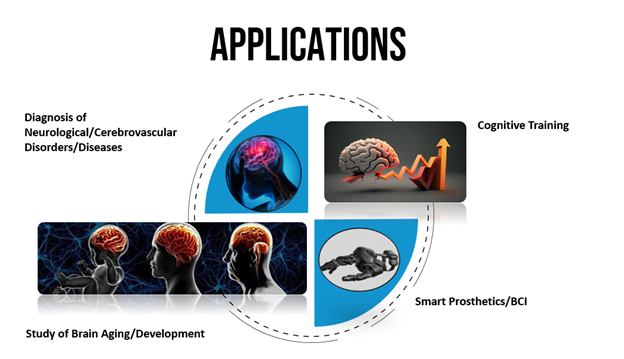

While fundamental research lays the groundwork, the ultimate goal is to translate insights into tools that improve patient care. In this realm, AI has become indispensable.

Beyond diagnostics, neuroscience is pioneering new modalities for rehabilitation and enhancement:

- Brain–Computer Interfaces (BCIs) and Neurofeedback

Wearable EEG devices combined with real-time feedback enable users to train attention, manage stress, and support recovery after brain injury. - Virtual and Augmented Reality

Immersive environments are being developed for exposure therapy, skill learning, and cognitive rehabilitation, offering controlled, adaptable stimuli that engage neural plasticity. - Personalized Neurotherapies

Integrating brain imaging, genetic profiling, and AI-driven analytics, researchers aim to tailor interventions—whether pharmacological or electromagnetic—to each individual’s unique neural signature.

By weaving together developmental insights, cognitive frameworks, and AI-driven clinical tools, this narrative demonstrates the breadth of modern neuroscience. Each figure underscores pivotal breakthroughs, while the prose guides readers through a coherent journey—from embryonic neurons to personalized therapies.